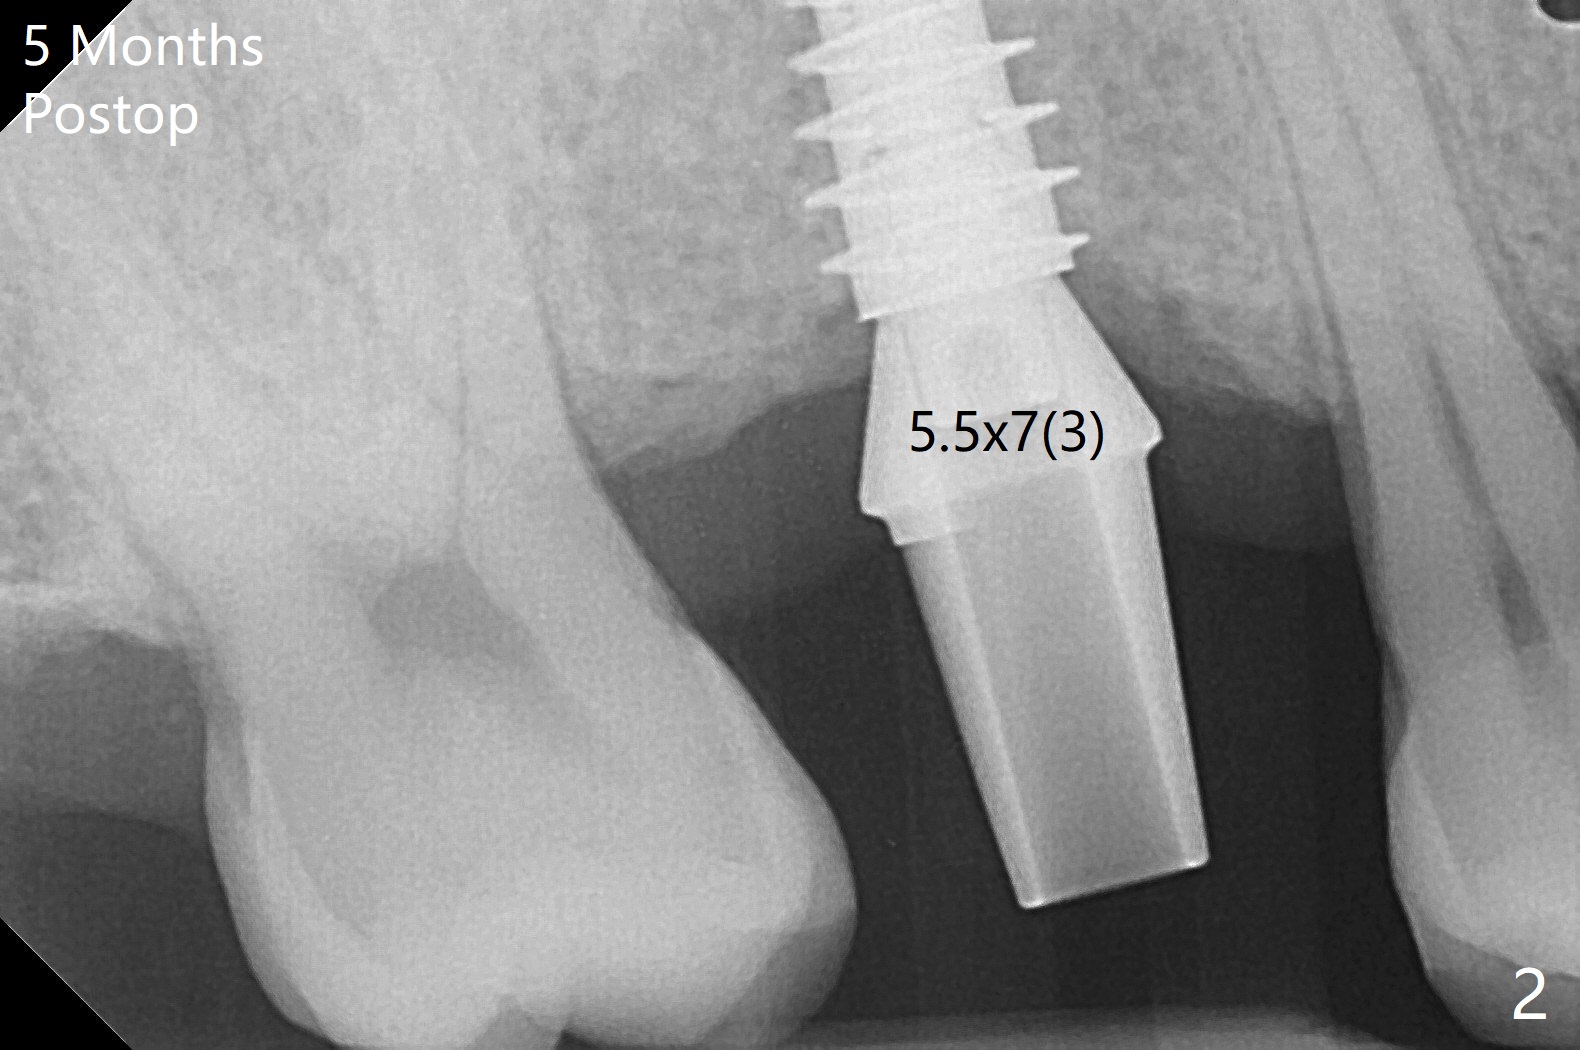

由于冠状病毒流行,右上六种植推迟七个月。老导板用起来好像挺顺手,植体位置仿佛正常(图一)。使用6毫米profile钻头后,放置6x3毫米愈合基台。术后5.5个月放置修复基台(图二),基台直径再小一号,放置就可能容易些,容易就位。